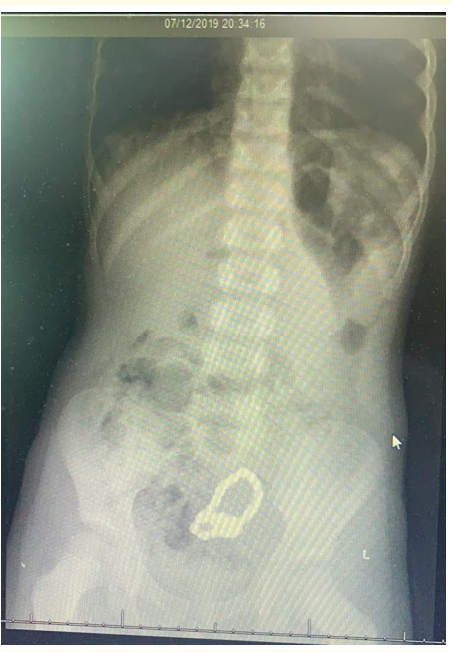

An Unusual Presentation of Chronic Intestinal Fistula - A Forgotten Multiple Magnet Ingestion

Nazima Chaudhary, Dinesh Banur Onkarappa, Naavarasu Sundaramurthy and Sleiman Gebran. 12(2): 38-42.